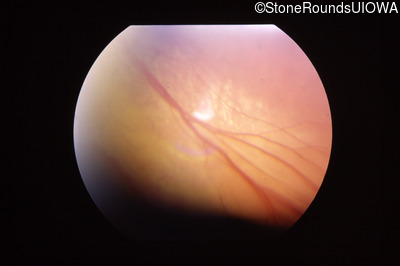

Fundus Photography - Right - No Light Perception

Fundus Photography - Left - 20/25 +2

Fundus Photography - Left - 20/32 -1